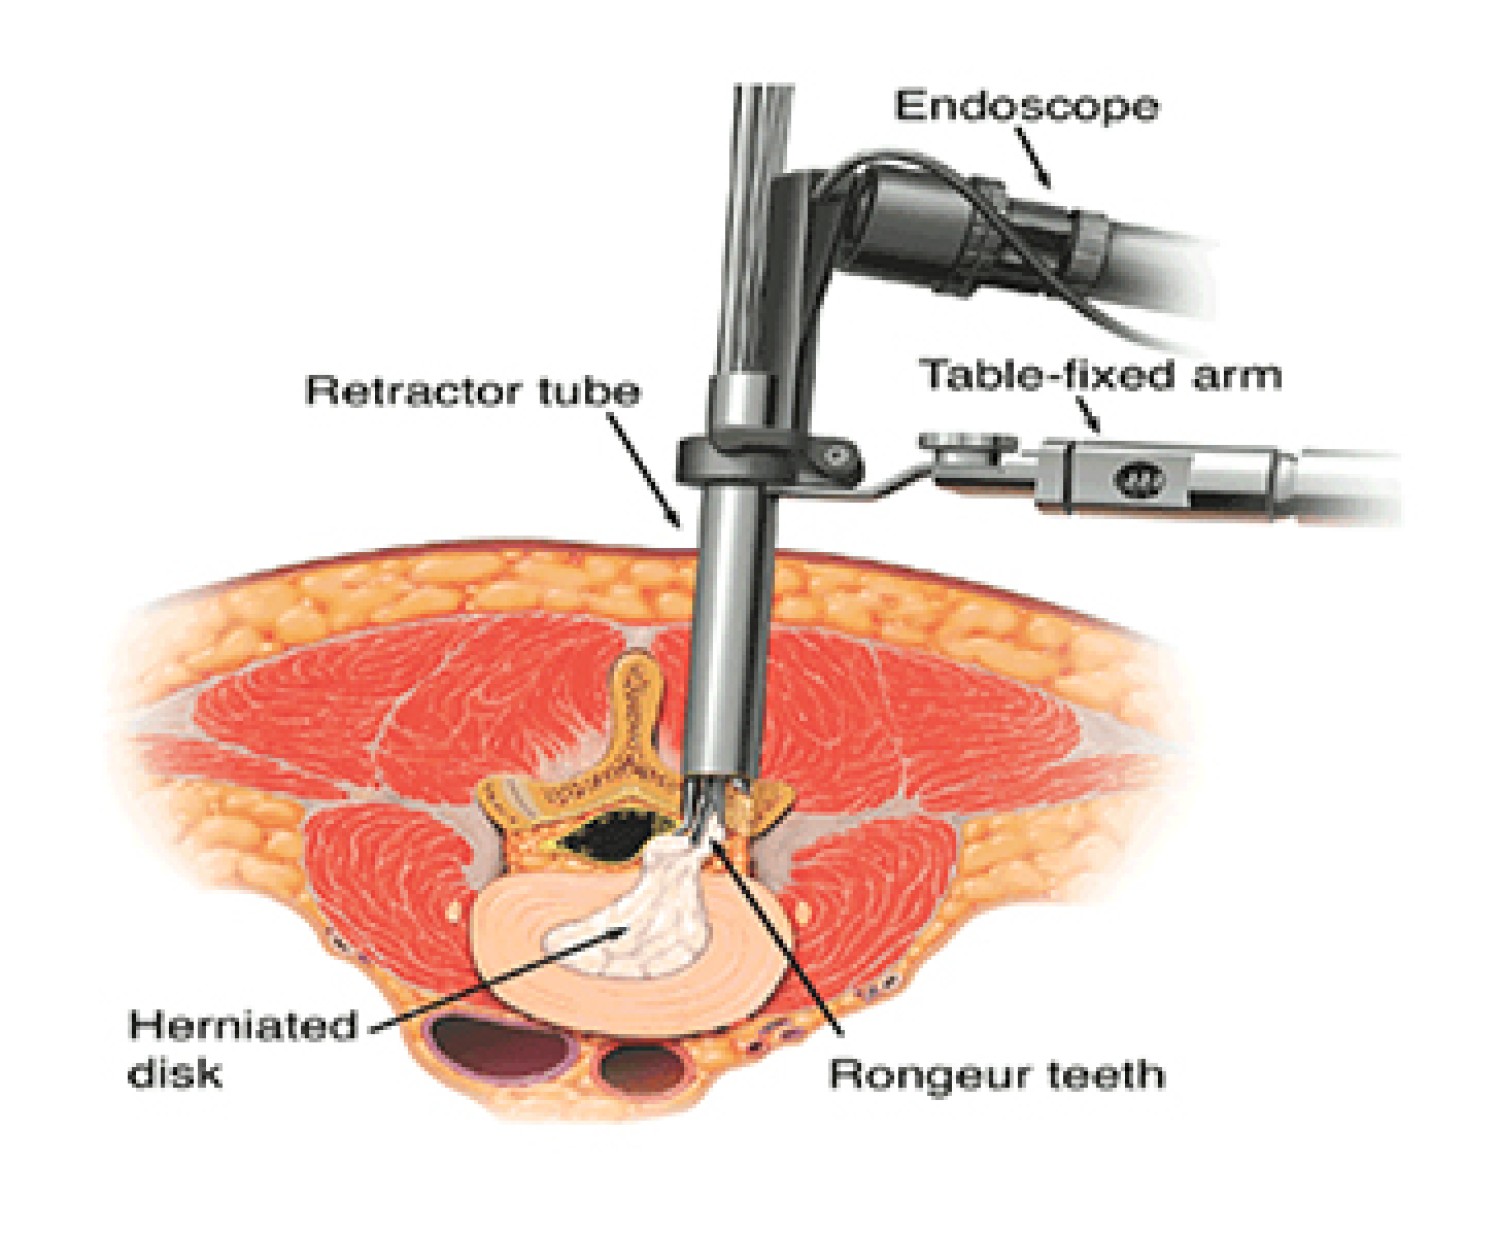

Minimally Invasive Spine Surgery